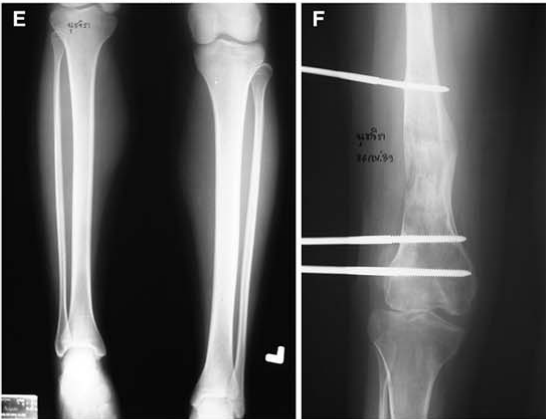

伊利扎洛夫骨延长技术。A.伊利扎洛夫骨延长法;B.在短缩骨干的上部做截骨;C.术后2周后,每天以1 mm距离牵拉延长截骨远端。

伊利扎洛夫的骨延长技术可以说实现了骨科「四维矫形」的完美理念,即三维外固定+时间变量(每天1 mm牵拉)。

伊利扎洛夫的骨延长技术不仅能延长和增粗管状骨。而目还能延长扁骨和不规则骨。